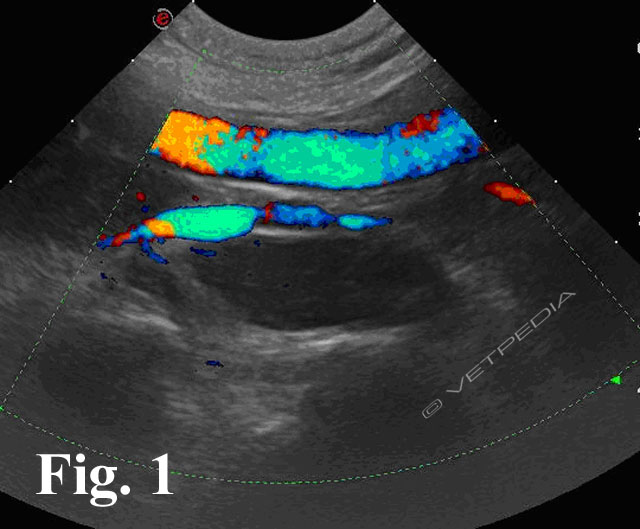

{{/_source.additionalInfo}}L’ecografia rappresenta una delle metodiche più sensibili per lo studio dei linfonodi addominali e permette di studiare la loro forma, le dimensioni, l’ecostruttura e l’ecogenicità. In tabella 1 sono riportati i linfonodi che drenano gli organi viscerali e le strutture parietali1. LINFONODI VISCERALI LINFONODI PARIETALI Lin